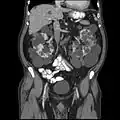

Abdominal CT scan of an adult with autosomal dominant polycystic kidney disease: Extensive cyst formation is seen over both kidneys, with a few cysts in the liver, as well. (Coronal plane)